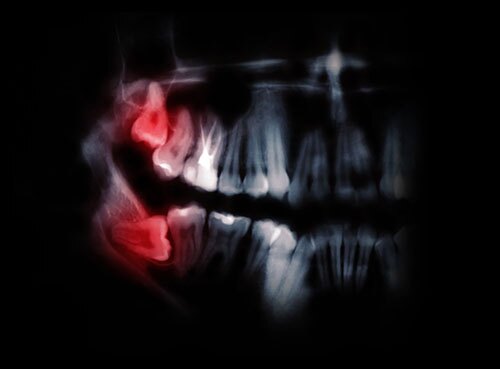

Signs of Impacted Wisdom Teeth

Signs and symptoms of impacted wisdom teeth are pain, swelling face and neck, bad taste in mouth and infection. If your wisdom teeth are impacted you may have any number of these symptoms or no symptoms at all. It is important to see a dentist at the first sign of any of these symptoms to address the problem.

Wisdom teeth will be recommended for removal if they are under the gum and bone and have no room to erupt and may be in a vulnerable spot that could cause problems such as future infection or cavities on neighbouring teeth. To have the wisdom teeth extracted, you will see either your dentist or an oral surgeon and be either awake or asleep using intravenous sedation. Various tools will be used to take the wisdom teeth out of the gums and bone, and the extraction sites will be sutured up. The healing time is typically just a few days.